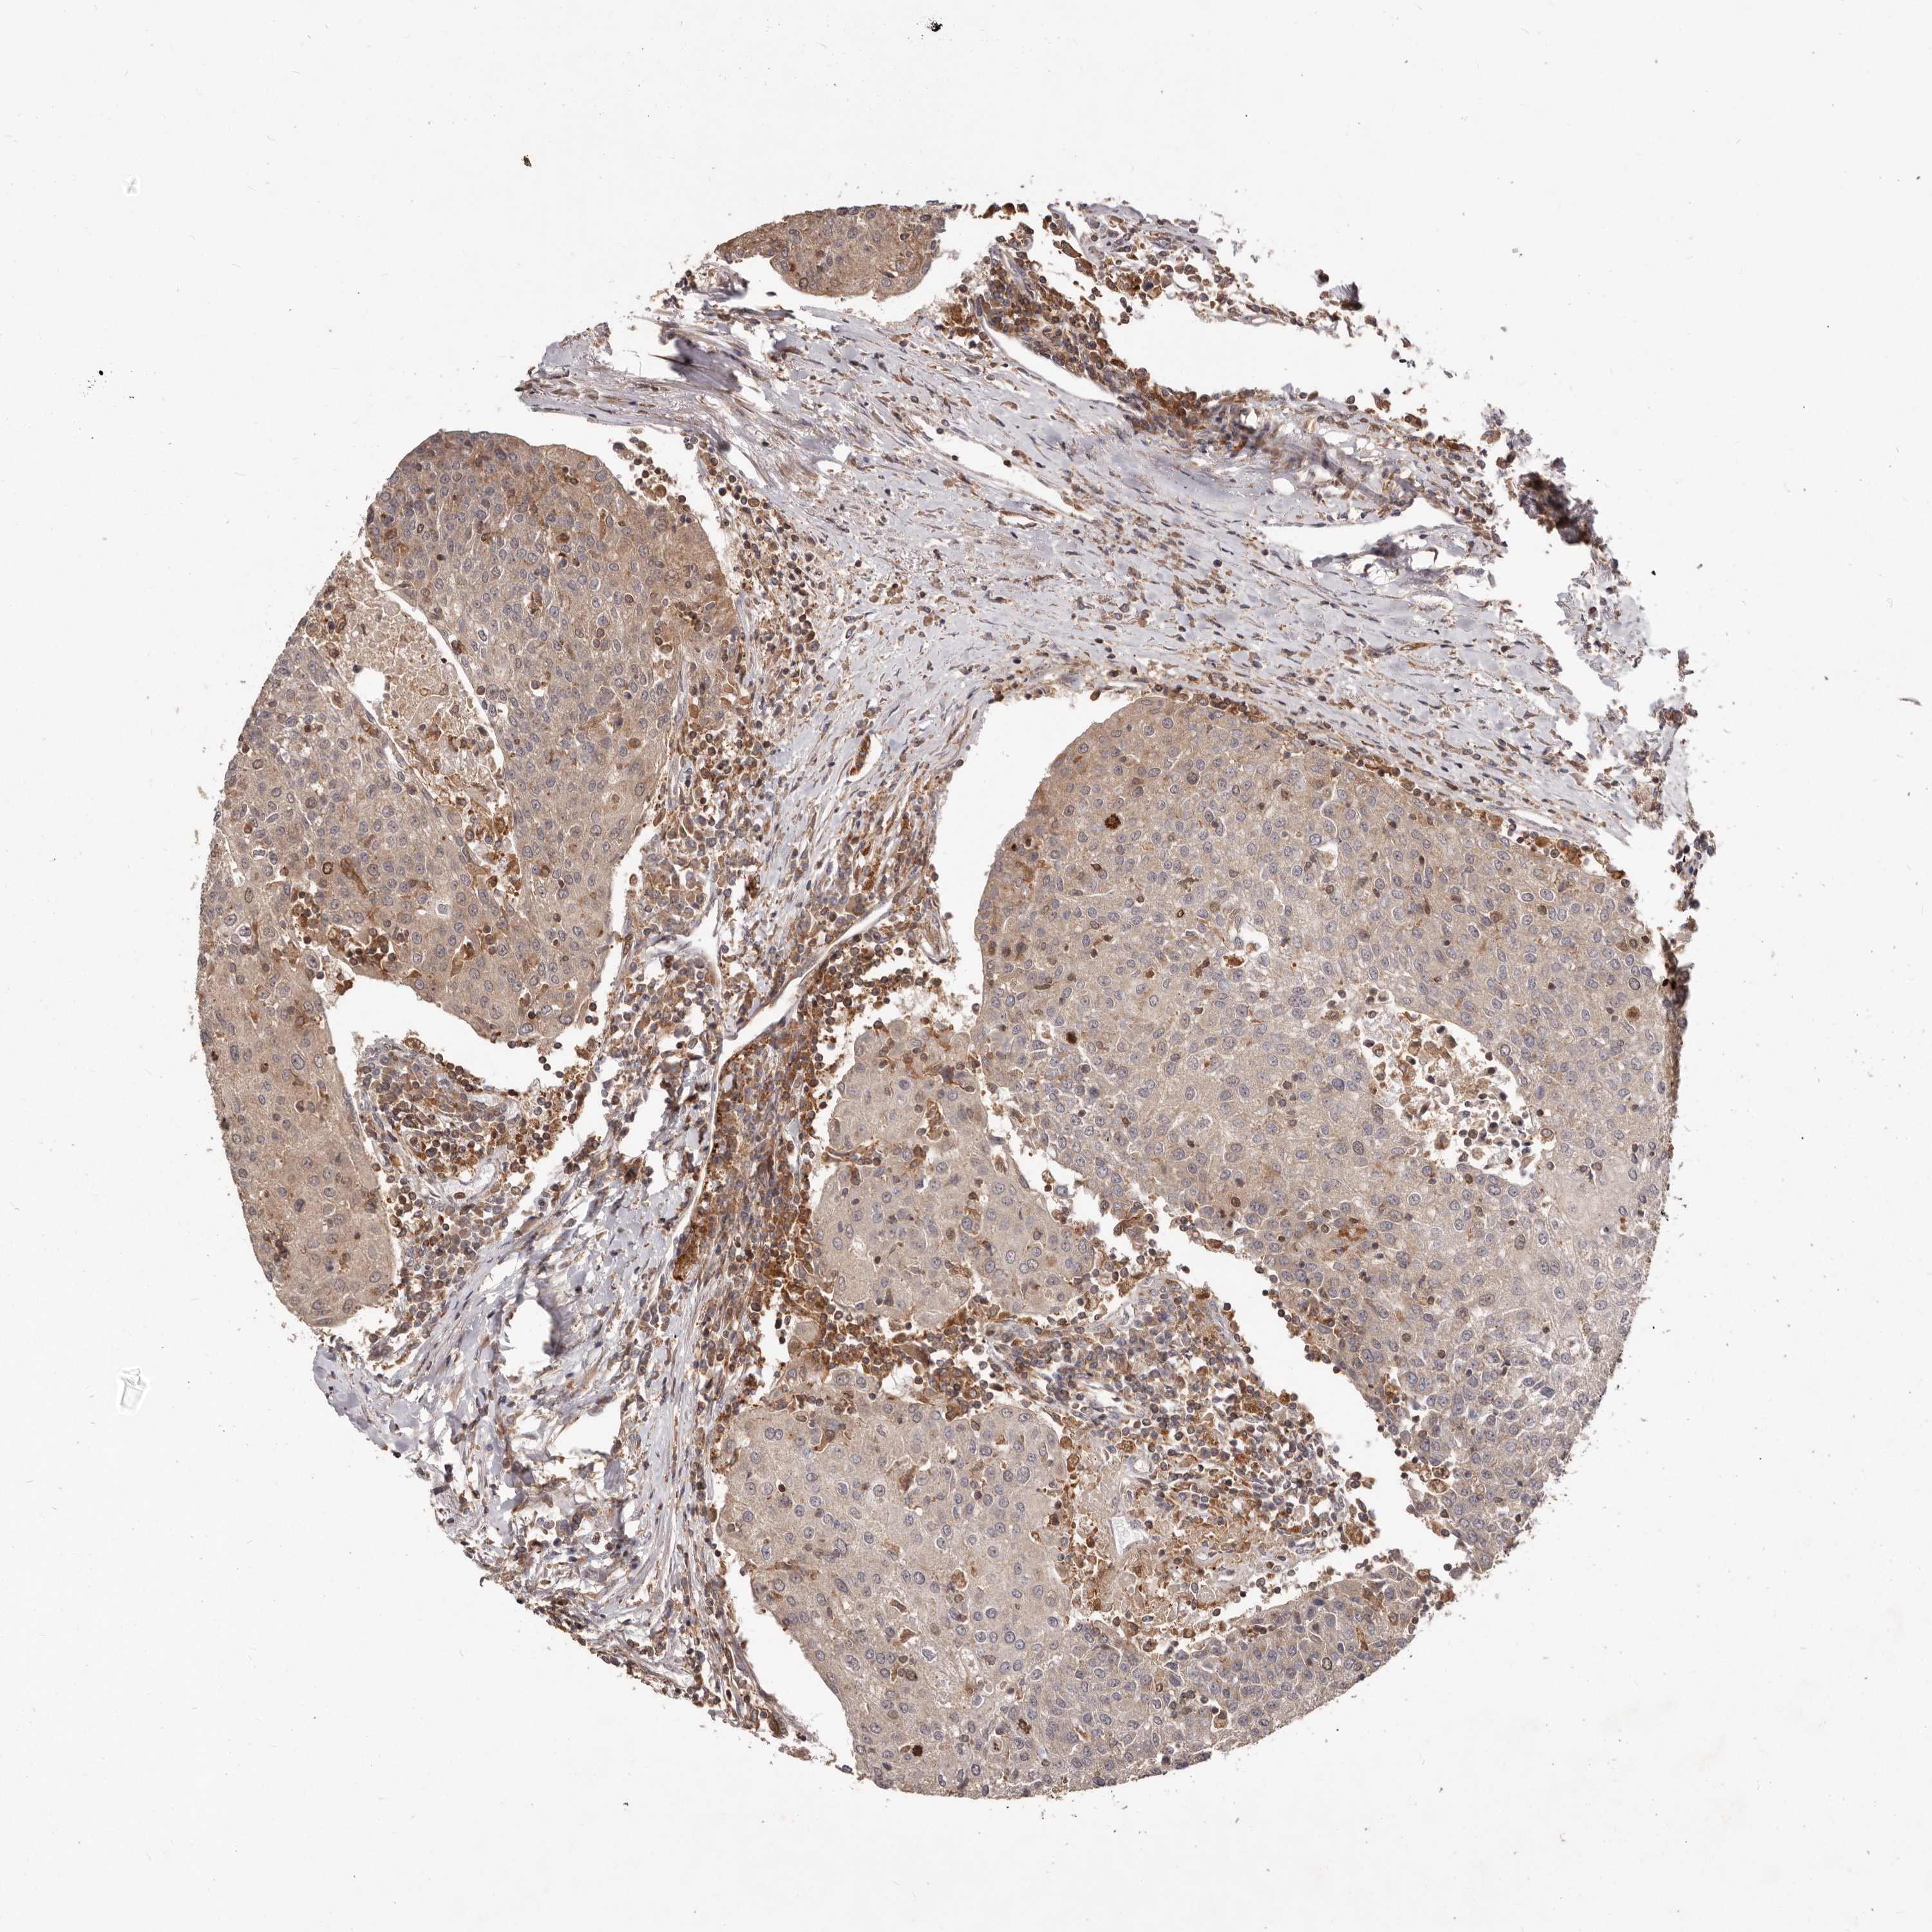

UROTHELIAL CANCER - Protein expressioni

A mouse-over function shows sample information and annotation data. Click on an image to view it in a full screen mode. Samples can be filtered based on level of antibody staining by selecting one or several of the following categories: high, medium, low and not detected. The assay and annotation is described here.

Note that samples used for immunohistochemistry by the Human Protein Atlas do not correspond to samples in the TCGA dataset.

Antibody stainingi

Antibody staining in the annotated cell types in the current human tissue is reported as not detected, low, medium, or high, based on conventional immunohistochemistry profiling in selected tissues. This score is based on the combination of the staining intensity and fraction of stained cells.

Each image is clickable and will lead to virtual microscopy that enables deeper exploration of all samples and also displays staining intensity scores, fraction scores and subcellular localization as well as patient and tissue information for each sample.

Antibody HPA030098

Staining

High

Medium

Low

Not detected

Intensity

Strong

Moderate

Weak

Negative

Quantity

>75%

75%-25%

<25%

None

Location

Nuclear

Cytoplasmic/membranous

Cytoplasmic/membranous,nuclear

Urothelial carcinoma, Low grade

Urothelial carcinoma, High grade